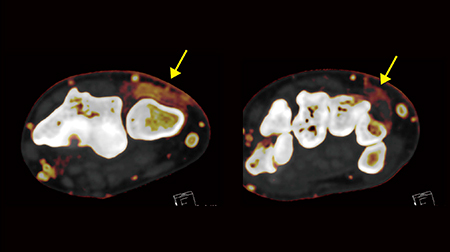

また,本症例では,第1指と第2指の中手骨頭背側に伸筋腱周囲炎を認め(図4↓),さらに冠状断像,横断像を併せて読影することで,MCP関節やPIP関節の滑膜炎を指摘できた(図5 ←)。DECTでは,アーチファクトの少ない複数断面の画像を作成でき,放射線科医としても自信を持って評価することが可能である。

図5 症例2:多断面による評価